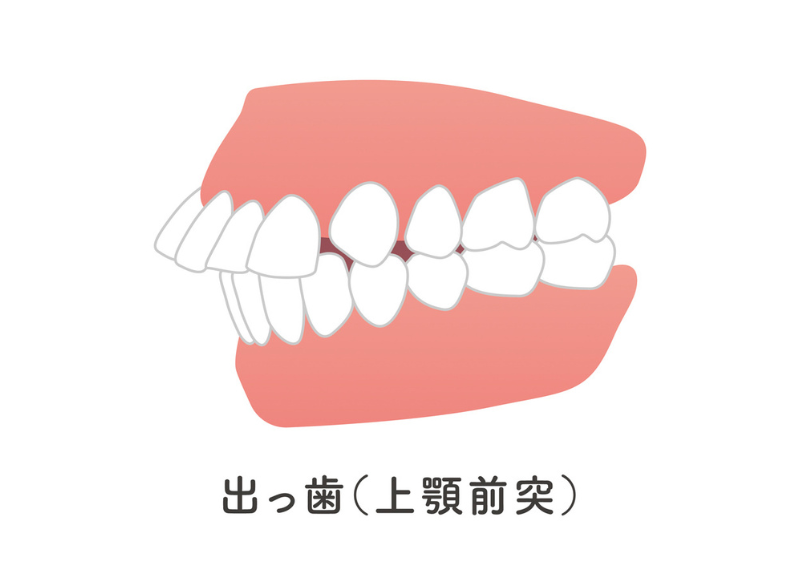

2. 出っ歯(上顎前突)

上の前歯が大きく前に出ている状態です。前歯が生え変わる時期(7歳〜9歳頃)にご相談いただくことが多いです。

転倒した際に前歯を折るリスクも高いため、早めの対策が有効です。

下顎の成長が不足している場合は、ファンクショナル・アプライアンスなどで成長を促します。